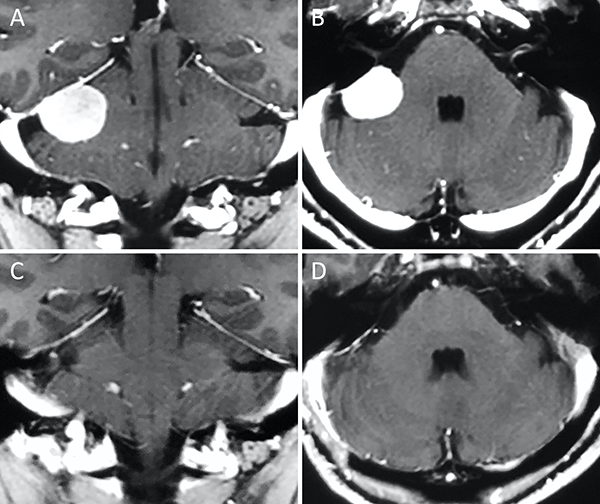

Figura 1. Meningioma tentorial medial. A-B: RM preoperatoria; C-D: RM postoperatoria.